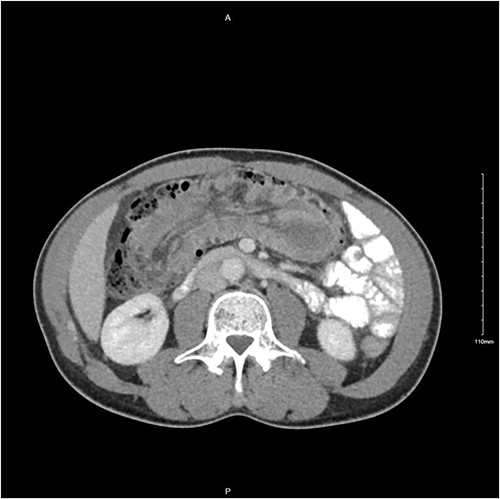

A 56-year-old male was diagnosed with a 4-day history of worsening, cramping left-sided lower abdominal pain and persistent vomiting. The patient had experienced intermittent bouts of similar pain in the previous few months; however, the sustained nature of the pain on this occasion prompted his presentation. Clinical examination elicited lower abdominal tenderness, most marked in the right para-umbilical region. He was an otherwise healthy patient, with no pertinent medical history. Initial investigations revealed a white cell count of 11.78 × 109/L with an associated mild neutrophilia of 9.29 × 109/L. His C-reactive protein was significantly elevated at 130 mg/L, with remaining haematological tests otherwise unremarkable. A computed tomography (CT) scan with intravenous contrast of the abdomen and pelvis was performed which identified a long segment (21 cm) of intussusception involving the distal small bowel, caecum and ascending colon and entirety of transverse colon, including mesentery (Fig. 1). A 5.5-cm hypodense mass was noted within the splenic flexure of the transverse colon which acted as a lead point for intussusception (Fig. 2). There was no pathological small bowel dilatation. Radiologically, the suggested differential diagnosis included gastrointestinal stromal tumour, carcinoid tumour, leiomyosarcoma, lymphoma or benign pathologies such as leiomyoma. The patient proceeded to theatre whereby a formal resection by means of extended right hemicolectomy and primary anastomosis was performed. Histological analysis demonstrated an ileal myxoma to be the causative pathology. The patient had an unremarkable post-operative course and was discharged well 1 week post-operatively.

Transverse CT image of small bowel intussusception into the ascending colon.